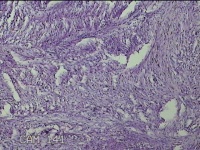

左大腿皮下结节

性别

女

年龄

30岁

临床诊断

皮下结节

一般病史

发现左大腿皮下结节1年余。

标本名称

大体所见

灰白粉红色组织1.7x0.8x0.3cm一个,表面带梭形皮肤 1.3x0.7cm,皮下见结节1.7x0.7cm一个,切开结节呈实性,切面灰白灰白粉红色,质中。

图2

良性病变。